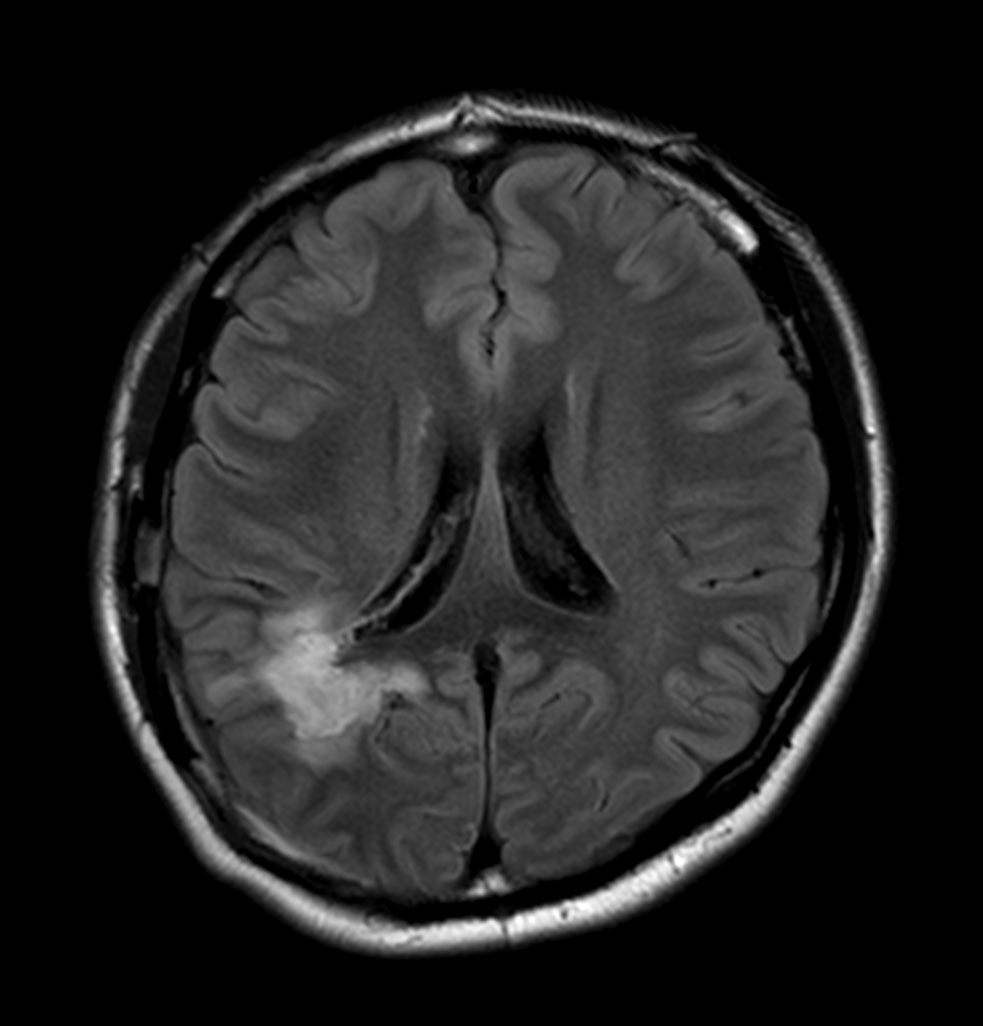

Axial T2w FLAIR